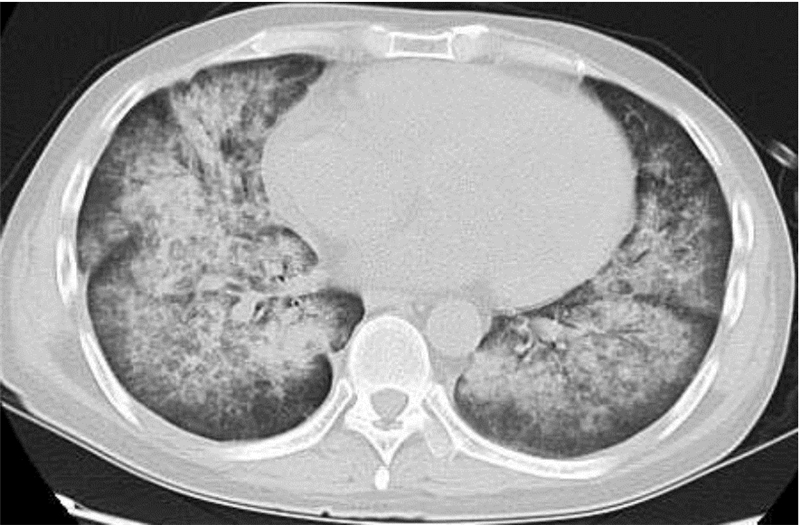

1 资料与方法例1患者,男,36岁,2011年6月确诊为淋巴肉瘤白血病(T细胞性),经予VDLP方案化疗1个疗程达完全缓解,遂于2012年3月30日予Ara-C+BUCY+MeCCNU预处理化疗,4月7日回输“B”型外周血干细胞共计358 mL,MNC计数 11.35×108/kg,CD34+细胞计数 15.12×106/kg。移植期间予环孢素A、吗替麦考酚酯、甲氨蝶呤等预防移植物抗宿主病(GVHD),移植后15 d中性粒细胞>0.5×109/L,16 d血小板>20×109/L,移植过程顺利。出院后继续服用环孢素A、吗替麦考酚酯抗排异,37 d出现皮肤GVHD;查血常规:白细胞 1.1×109/L,血红蛋白 64 g/L,血小板 6×109/L;复查骨髓常规,提示无骨髓小粒,有大量脂肪滴,有核细胞量显著减少;STR示供受者混合嵌合,自身29.9%,供者特异性20.3%,两者相同49.8%; 60 d复查血常规:白细胞 4.0×109/L,血红蛋白 78 g/L,血小板 7×109/L;骨髓常规示白血病复发,STR示植入不良,拟行二次移植,但无合适供者。73 d出现发热(体温39.2 ℃)、咳少量白色黏嗽,双肺未闻及明显干湿性啰音;查血常规:白细胞 0.1×109/L,血红蛋白 69 g/L,血小板 4×109/L;C反应蛋白 46.4 mg/L。拟诊:肺部感染,DAH疑诊。给予美罗培南、万古霉素抗细菌,卡泊芬净抗真菌,甲强龙80 mg 静推,每8 h一次减少渗出。80 d出现咯血、胸闷、呼吸困难,双肺可闻及湿啰音及散在干啰音;血常规:白细胞 0.1×109/L,血红蛋白 58 g/L,血小板 1×109/L;(吸氧5 L/min)血气分析:pH 7.3,PCO2 31 mmHg(1 mmHg=0.133 kPa),PaO2 78 mmHg,氧饱和度83%;血凝分析各项指标正常;查胸部CT(图 1):两肺可见弥漫性对称分布斑片状高密度模糊,部分融合呈片,间质增厚,部分较实,且见胸膜下回避征象。诊断:DAH。予无创呼吸机供氧,甲强龙500 mg 静推 每8 h一次及抗感染、输血制品等治疗,之后患者氧饱和度逐渐下降,97 d因呼吸衰竭而死亡。

| 图 1 例1 +80 d肺部CT示两肺弥漫性病变 |